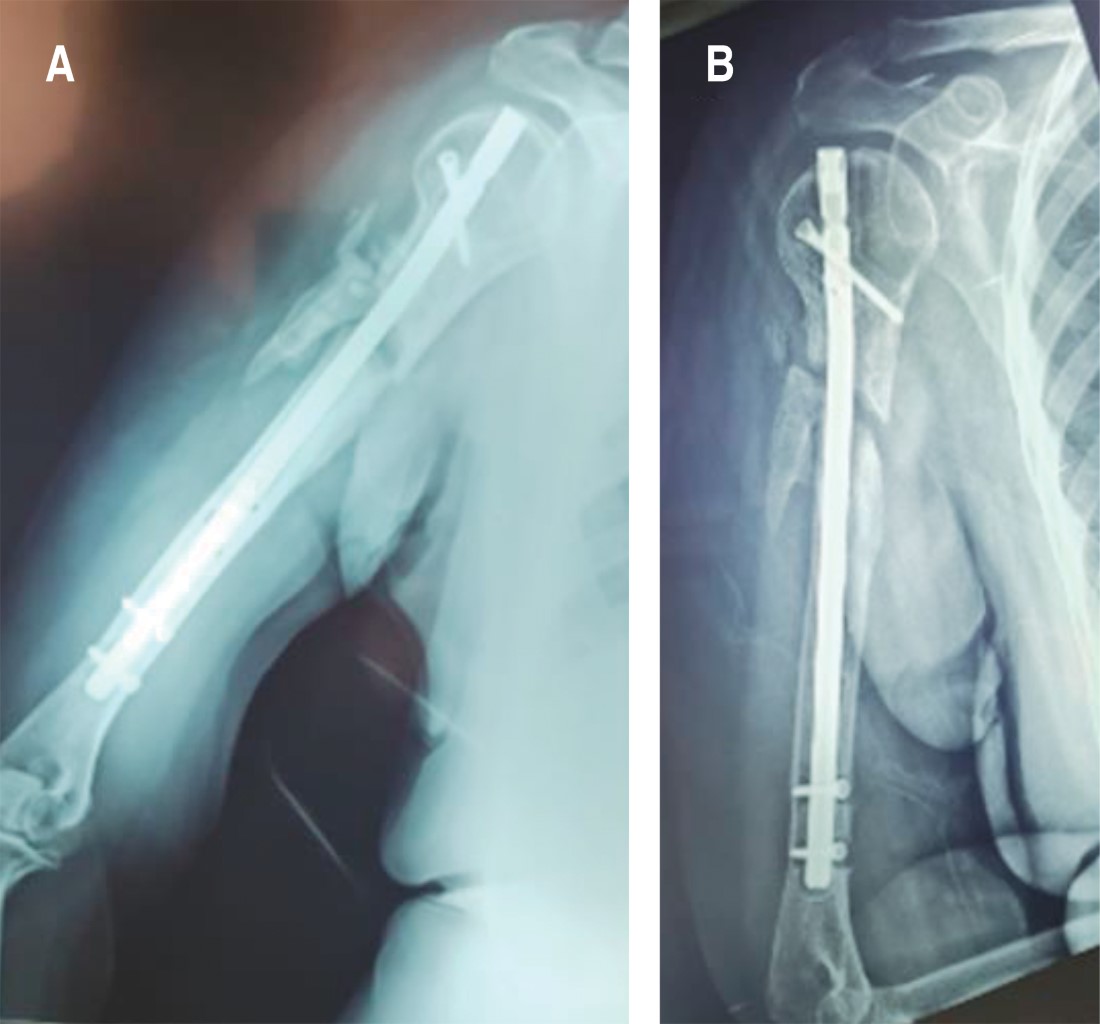

Introduction: different techniques have been described for the treatment of nonunion. However, there are very few reports on the use of autologous tricortical iliac crest graft. The objective of reporting this case is to emphasize the importance of using the autologous tricortical iliac crest graft, in the context of the "diamond concept", after 3 failed surgeries for humerus nonunion. Case report: female, 69 years old, type 2 diabetes mellitus, grade III obesity, diagnosis of aseptic oligotrophic nonunion of the right humerus plus radial nerve injury, underwent 3 previous surgeries without success in resolution. The treatment consisted of performing osteosynthesis with an locking compression plate (LCP) for the proximal humerus and application of the "diamond concept" through the use of autologous tricortical iliac crest graft, bone marrow aspirate, platelet-rich plasma and demineralized bone matrix, as well as exploration and decompression of the radial nerve, achieving complete consolidation and functional recovery. Conclusion: after 3 failed surgeries, and after a bone loss of 7 cm, complete bone consolidation and full functional recovery are achieved through the application of the "diamond concept" with the complement of the use of autologous tricortical iliac crest graft.

Figure 1